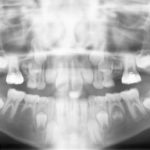

Intercettare l’inclusione del canino superiore mediante estrazione precoce del canino deciduo Premium

Viene valutata clinicamente la validità dell’estrazione precoce dei canini decidui in dentatura mista per prevenire l’inclusione dei canini permanenti. Lo studio si è svolto analizzando le ortopantomografie di quattro pazienti per un totale di sei canini, a distanza di circa 14 mesi dopo l’estrazione del canino deciduo.